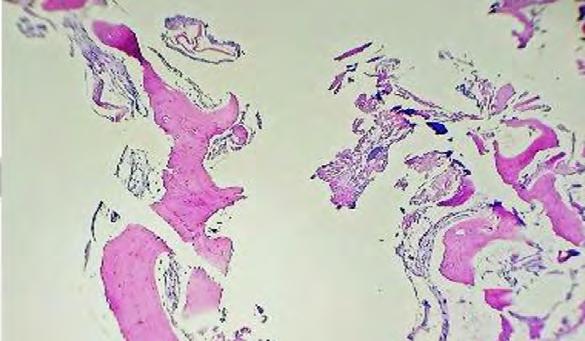

El estudio histopatológico de este quiste sobre el contenido líquido de la cavidad puede mostrar acelularidad o escasas células de tejido conectivo, así como eritrocitos y el estudio de la pared de la cavidad mostrará solo hueso vital y libre de tejido epitelial, por lo cual se determina como una lesión no quística a pesar de recibir dicho nombre.10,12

En los cortes histológicos examinados se observan trabéculas de tejido óseo lamelar maduro con diferentes grados de mineralización con respectivos espacios medulares entremezclado con escaso tejido conjuntivo fibroso denso bien vascularizado compatible con el QOS (Figura 5).

Figura 5. Corte histopatológico de pared de la cavidad con hueso vital, libre de capsula de tejido epitelial. cumplen con el objetivo diagnóstico además de terapéutico, por lo que no es necesario ninguna otra medida adicional.19